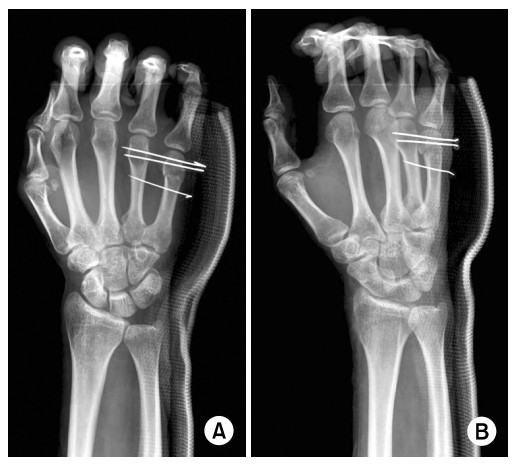

개인 신상정보를 담고 있어 부득이하게 익명 기능을 사용한 점 양해 부탁 드립니다. 3주 전 오른손 제5수지(오른손 새끼손가락쪽) 중수골 경부골절 진단을 받고 k-강선 4개를 횡으로 삽입하는 수술을 하였습니다. 지금은 강선 유지중인 상태로 지난 주말부터 주치의(수술해주신 선생님)에게 허락받고 나서 손을 계속 움직이고 있습니다. 움직일 수 있는 범위내에서는 전부 움직이고 있고 틈날때마다 쥐엇다 폈다라던가 손가락 관절을 계속 움직이고 있습니다. 물론 수술경과 및 적절한 재활운동에 대해서는 주치의 의견이 가장 정확하겠으나 상황상 주에 1회 정도밖에 주치의 진료를 받지 못하고 있어, 진료받기 전에 궁금한 내용이 있어 의료넷에 질문글을 쓰게 되었습니다. (사진은 제 사진이 아니며 인터넷 검색해서 관련 논문들 중 제 사진과 가장 유사한 것을 가져왔습니다) 1. 현재 주먹을 쥘 때 새끼손가락이 끝까지 쥐어지지 않습니다. 왼손으로 해보니 주먹을 꽉 쥐게되면 제5수지 중수골이 주먹 안쪽으로 말리면서 힘을 주게 되는데, 현재 사진처럼 제5수지 중수골과 제4수지 중수골이 강선으로 고정되어 있어서 주먹이 끝까지 안쥐어지는게 맞나요? 2. 반대로 손바닥을 쫙 펼 때, 마찬가지로 새끼손가락이 끝까지 펴지지 않습니다. 물론 어느정도 1자로 펴지기는 합니다만 제가 원래 손에 힘을 줘서 쫙 피게 되면 근위지골과 중간지골이 손등쪽으로 좀 올라갈 정도로 펴지는데.. 현재 중수골 경부골절이 된 오른손 새끼손가락만 그게 안됩니다. (나머지 오른손/왼손 손가락들은 다 됨) 3. 손가락의 외전(손가락 사이를 벌리는 것)과 내전(손가락 사이를 오므리는것)기능 역시 중수골 골절된 새끼손가락만 잘 안됩니다. 4. 위에 것들을 포함해서 중수골 경부 골절로 인해 강선을 횡으로 삽입해서 고정하는 수술을 하였을 때, 강선이 고정되어 있기 때문에 손 운동범위가 제한되는 게 맞을까요? 만약 강선이 고정되어 있기 때문에 제한되는 거면 손 움직이는 걸 너무 무리하게 하면 안될거 같은데, 만약 그게 아니라 3주동안 깁스를 하고 있어서 손 관절이 굳어 재활이 필요한 거라면 더 굳기 전에 좀 더 적극적으로 움직이는 게 맞을것 같고.. 일단 주치의는 반대쪽 손을 써서 억지로 움직이는 것은 하면 안된다고 했기 때문에 지금은 오른손 단독으로 최대한 힘을 줘서 움직일 수 있는 정도로 계속 하고 있습니다. 답변 미리 감사드립니다. 0